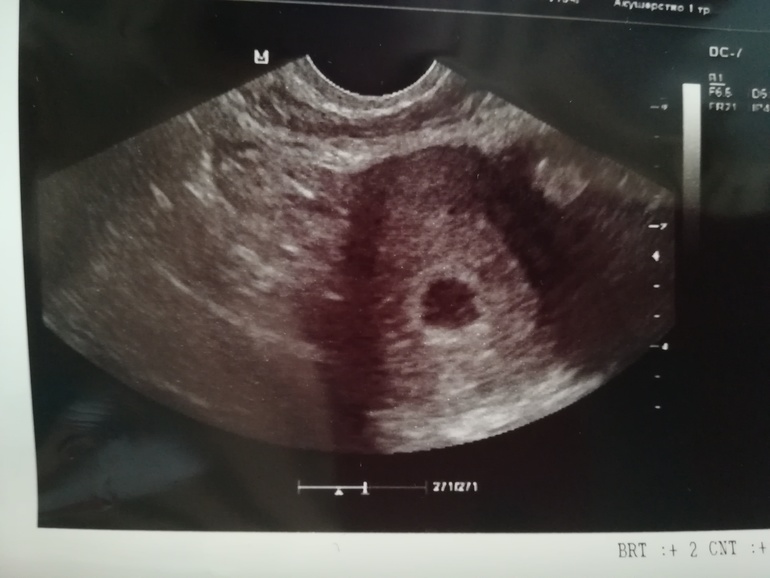

Какой хороший снимочек) А мне врач на узи сказала приходить только в конце 6 недели( Вот думаю чего раньше не напросилась.